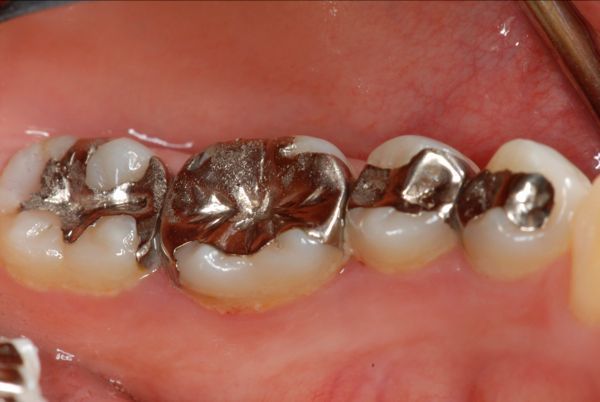

③アマルガム アマルガムの主な成分は水銀で、アレルギーを起こしやすいといわれています。まだ、レジン(プラスチック)が使用される20年以上前には頻繁に使用されていました。基本的に、当院では患者さんのすべてのアマルガムは除去しております。

左下6番目にメタルインレーが装着されていた。銀歯を除去して、保険適応の白い詰め物をした。数ヵ月後から皮膚症状の赤みが少なくなり目立たなくなった。

左下6番目に銀歯が装着されている。

銀歯を外して、虫歯を削ってから保険適応の詰め物をした。